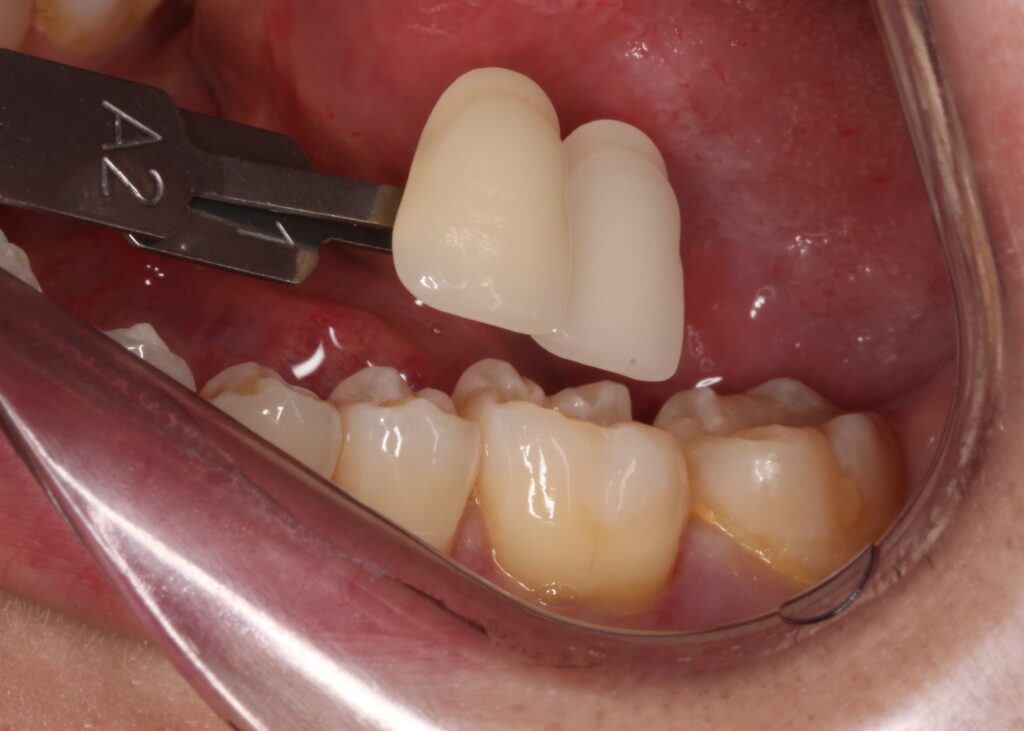

歯の色を色見本で確認します。その方の歯の色に合ったセラミックを専門の技工士が製作します。

後日セラミックが歯にセットされた状態です。

綺麗に歯にセットされています。どこを治療したか分かりますか?

歯の色に綺麗に仕上がり、ピッタリと歯と一体になっています。